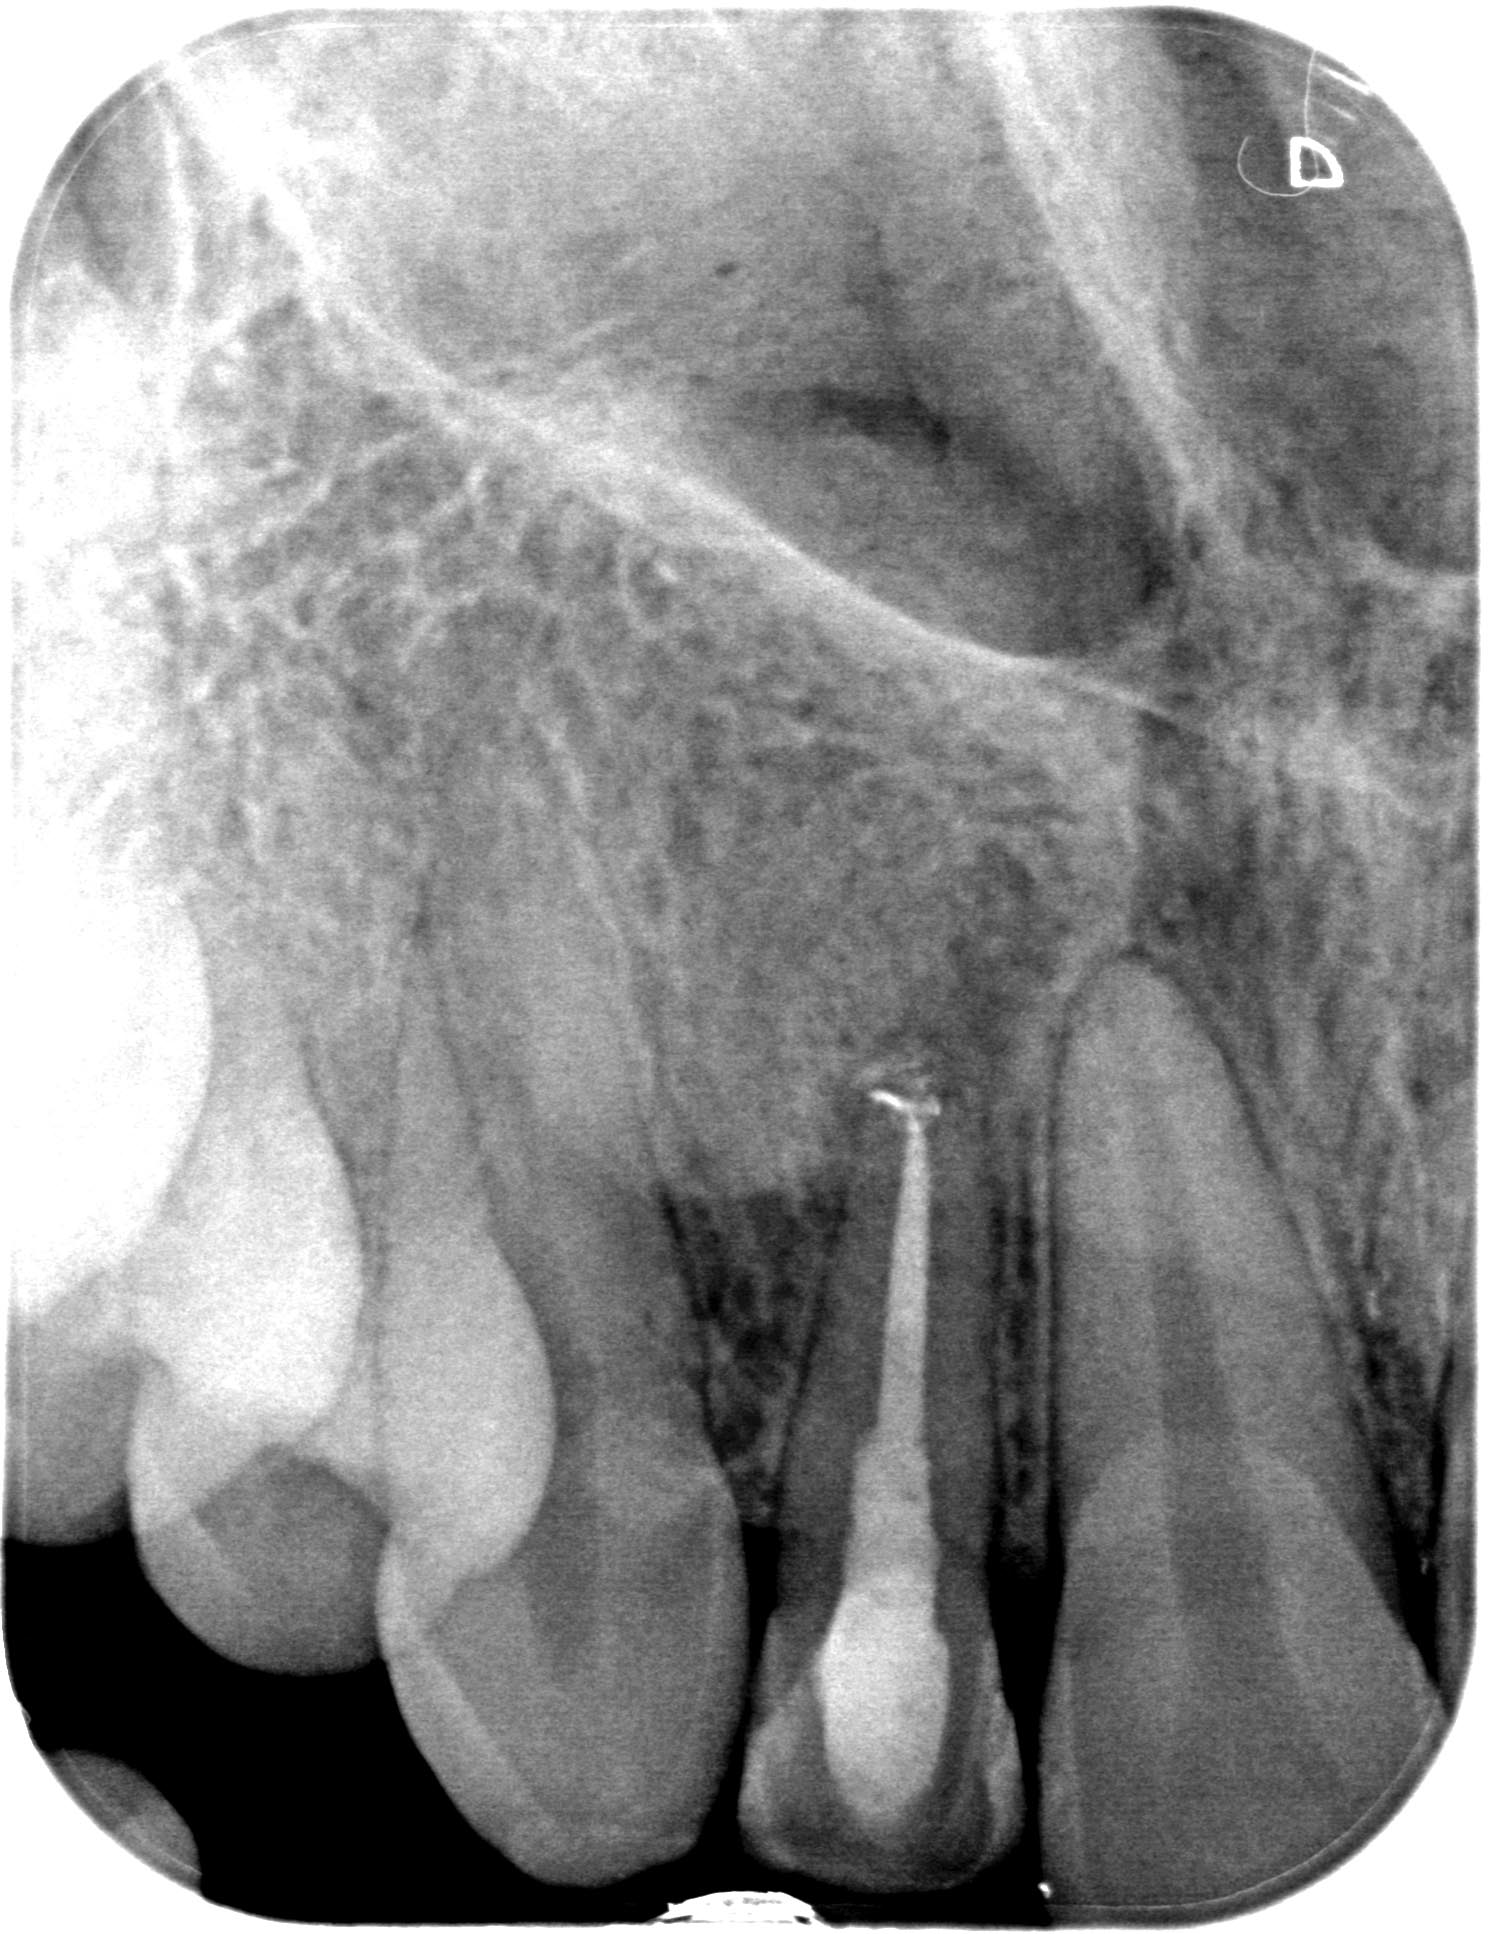

BL_12-1-2 Veröffentlicht 16. Dezember 2014 am 1488 × 1934 in Die eine geht, die andere kommt… (I) Zahn 12 WF- Kontrolle 6 Monate post WF